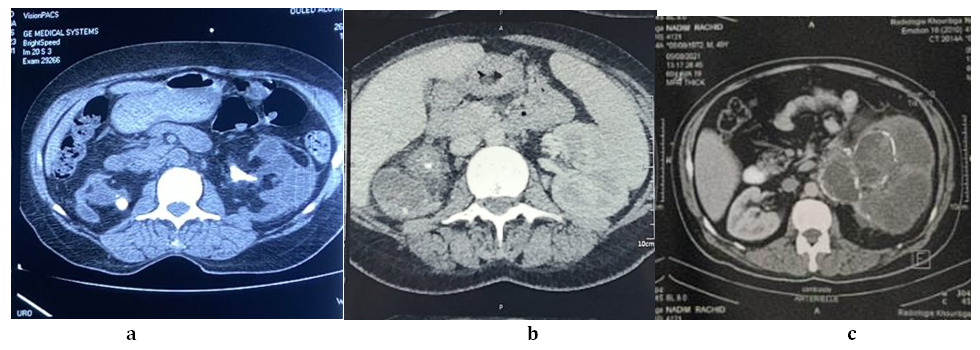

Radiologically, unpredicted x-rays of the urinary tract were routinely requested objectifying systematically. Radiolucent stones in 14 patients (33.33%). Renal ultrasound made it possible to suspect the diagnosis in 30 patients (71.42%), showing dilation of the pyelocaliceal cavities with finely echogenic content associated with the destruction of the renal parenchyma. Urinary CT scan confirmed diagnosis, often showing the image of the bear Paw, and indicating the etiology was lithiasis in 33 patients (78.57%), followed by Ureteropelvic junction (UPJ) in 5 patients (11.9%) then 3 case of compression by bladder tumor (7.14%) and 1 case retroperitoneal fibrosis (2.38%) (Figure 2).

Figure 2. CT images of pyonephrosis due to pyelic lithiasis (a,b) and to ureteropelvic junction (c).

Radiological examinations, such as ultrasound and CT scans, are essential for diagnosis [2-3]. Ultrasound demonstrates overall dilation of pyelocaliceal cavities, echogenic debris in urine, and parenchymal changes. CT scans aid in differentiating between hydronephrosis and pyonephrosis, determining the underlying condition (obstacle), and identifying features such as perirenal infiltration.